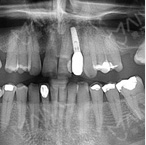

麦芽口腔种植系统均为原装进口;材料均获OHSMS1800健康安全认证以及ISO9000质量认证;享受5年甚至终生质保,并提供 养护。